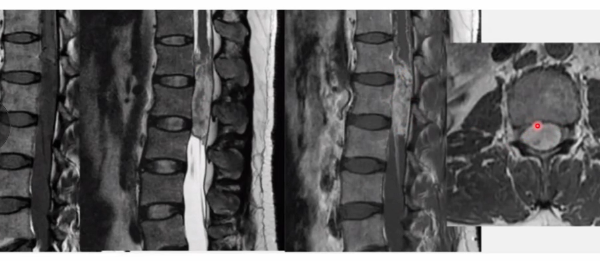

Ependimoma Medular

Características de imagem

Central ou LAteral?

Simétrico ou assimétrico

Impregnação de contraste?

É comum seringomielia?

É comum haver calcificação?

A

Centromedular

Simétrico

Impregnação heterogênea

Seringomielia (65% dos casos)

Pode haver calcificação

Pode ser circunscrito ou infiltrativo